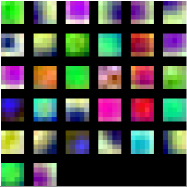

In order to assess the visual appearance of the deep learned features, a graphical representation of the 32 filters of size learned on the first layer of the CNN is presented in Figure 13. These representations allow to verify which types of high level characteristics are detected by the first layer of the network (Zeiler and Fergus, 2014). Thus, they are suitable to confirm if the network was trained for long enough, as well-trained CNNs usually display smooth filters without noisy patterns, as in this case. From Figure 13(a) it is possible to see that filters learned in Experiment 1 are mostly descriptors of the color properties of the lesions. This setting is in line with the fact that the training set used in this case contains not only small MAs but also medium size HEs, which can be more easily described in terms of their internal color homogeneity rather than their edges, which significantly varies from one to another. Other filters are able to capture purple, ellipsoidal structures corresponding to true lesions like those illustrated in Figure 5(b). This last type of filter is more common in the first layer of the CNN learned in Experiment 2 (Figure 13(b), which might be associated with the smaller true positive structures observed in the training set built with ROC and DIARETDB1 MAs.